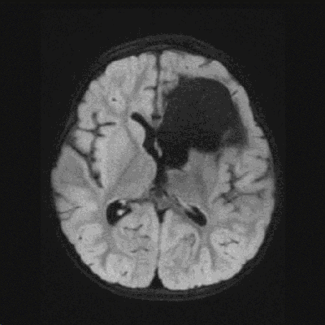

An MRI gave more details. Kaylee had three cavernous malformations on the left side of her brain — one the size of a baseball and two about a cherry. These abnormal clusters of blood vessels are not cancerous but can cause a host of neurological disorders, everything from dizziness and weakness to seizures and stroke.

“They’re usually not life threatening, although in the most extreme cases they can be,” said Sean Lew, MD, a Pediatric Neurosurgeon at Children’s Wisconsin. “But they can damage the brain and cause deficits.”